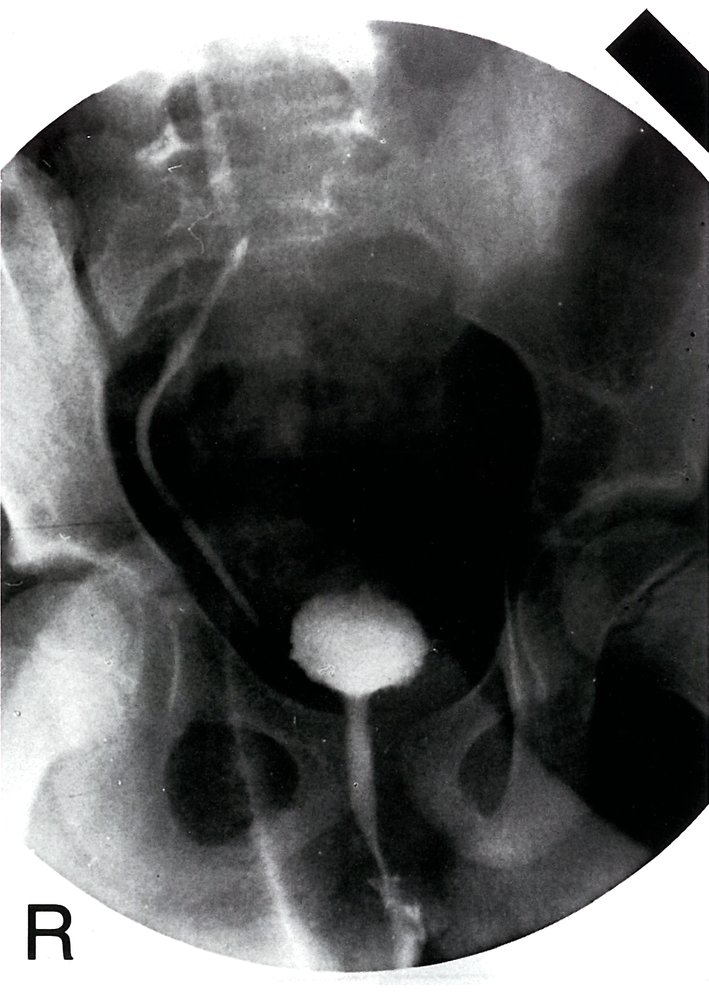

Voiding cystourethrography [2][5][14]

• Only used if there is high suspicion for VUR because of its invasive nature and use of radiation

• Potential findings include:

• Visualization of VUR (see ā€œDiagnostics of VURā€) [2][3]

• Obstructive uropathy (e.g., stenosis, hydronephrosis)